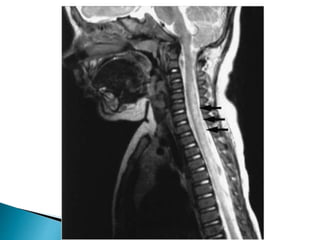

 MRI findings include focal and central high

signal areas in T2 sequences, occupying more

than two thirds of the spinal cord axially, and

extending over three to four segments,

generally in the thoracic spine.

 Spinal expansion may or may not be found

and, in general, there is contrast medium

enhancement, usually patch-like or diffuse.

 MRI findings are usually normal in 40% of

cases